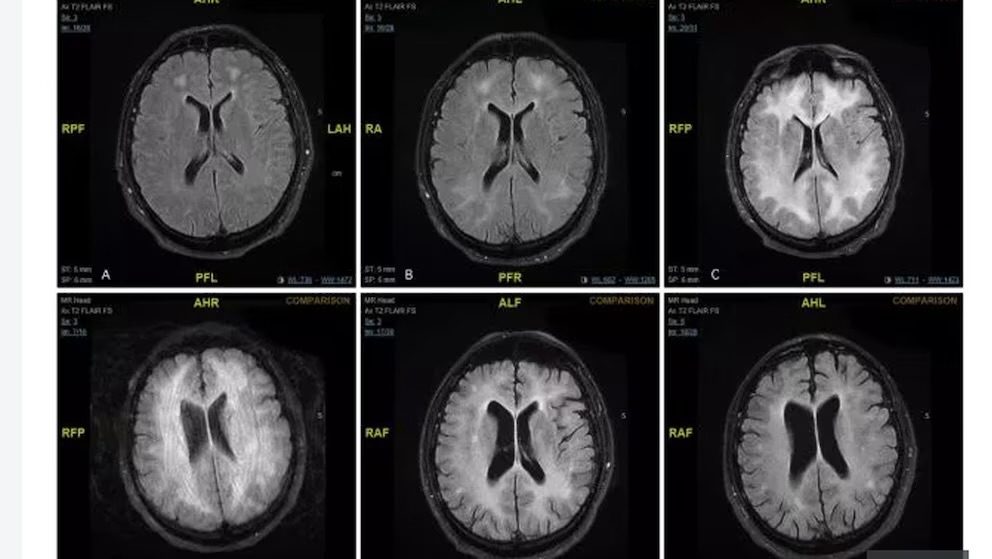

Las imágenes del cerebro obtenidas a través de estudios de resonancia magnética de un consumidor habitual de cocaína revelan el daño que la droga puede causar con el tiempo.

El paciente no identificado fue diagnosticado con una condición rara llamada leucoencefalopatía tóxica inducida por cocaína después de abusar regularmente durante años.

Los estudios fueron efectuados en el hospital de Msida, de Malta. Según los profesionales que atendieron al paciente, se trata de un hombre de 45 años que estaba confundido y se comportaba de manera extraña, antes de que los médicos se dieran cuenta de que padecía leucoencefalopatía tóxica inducida por cocaína.

Abdilla envió a su paciente para una resonancia magnética en su cerebro, que reveló daños en la sustancia blanca en el cerebro.